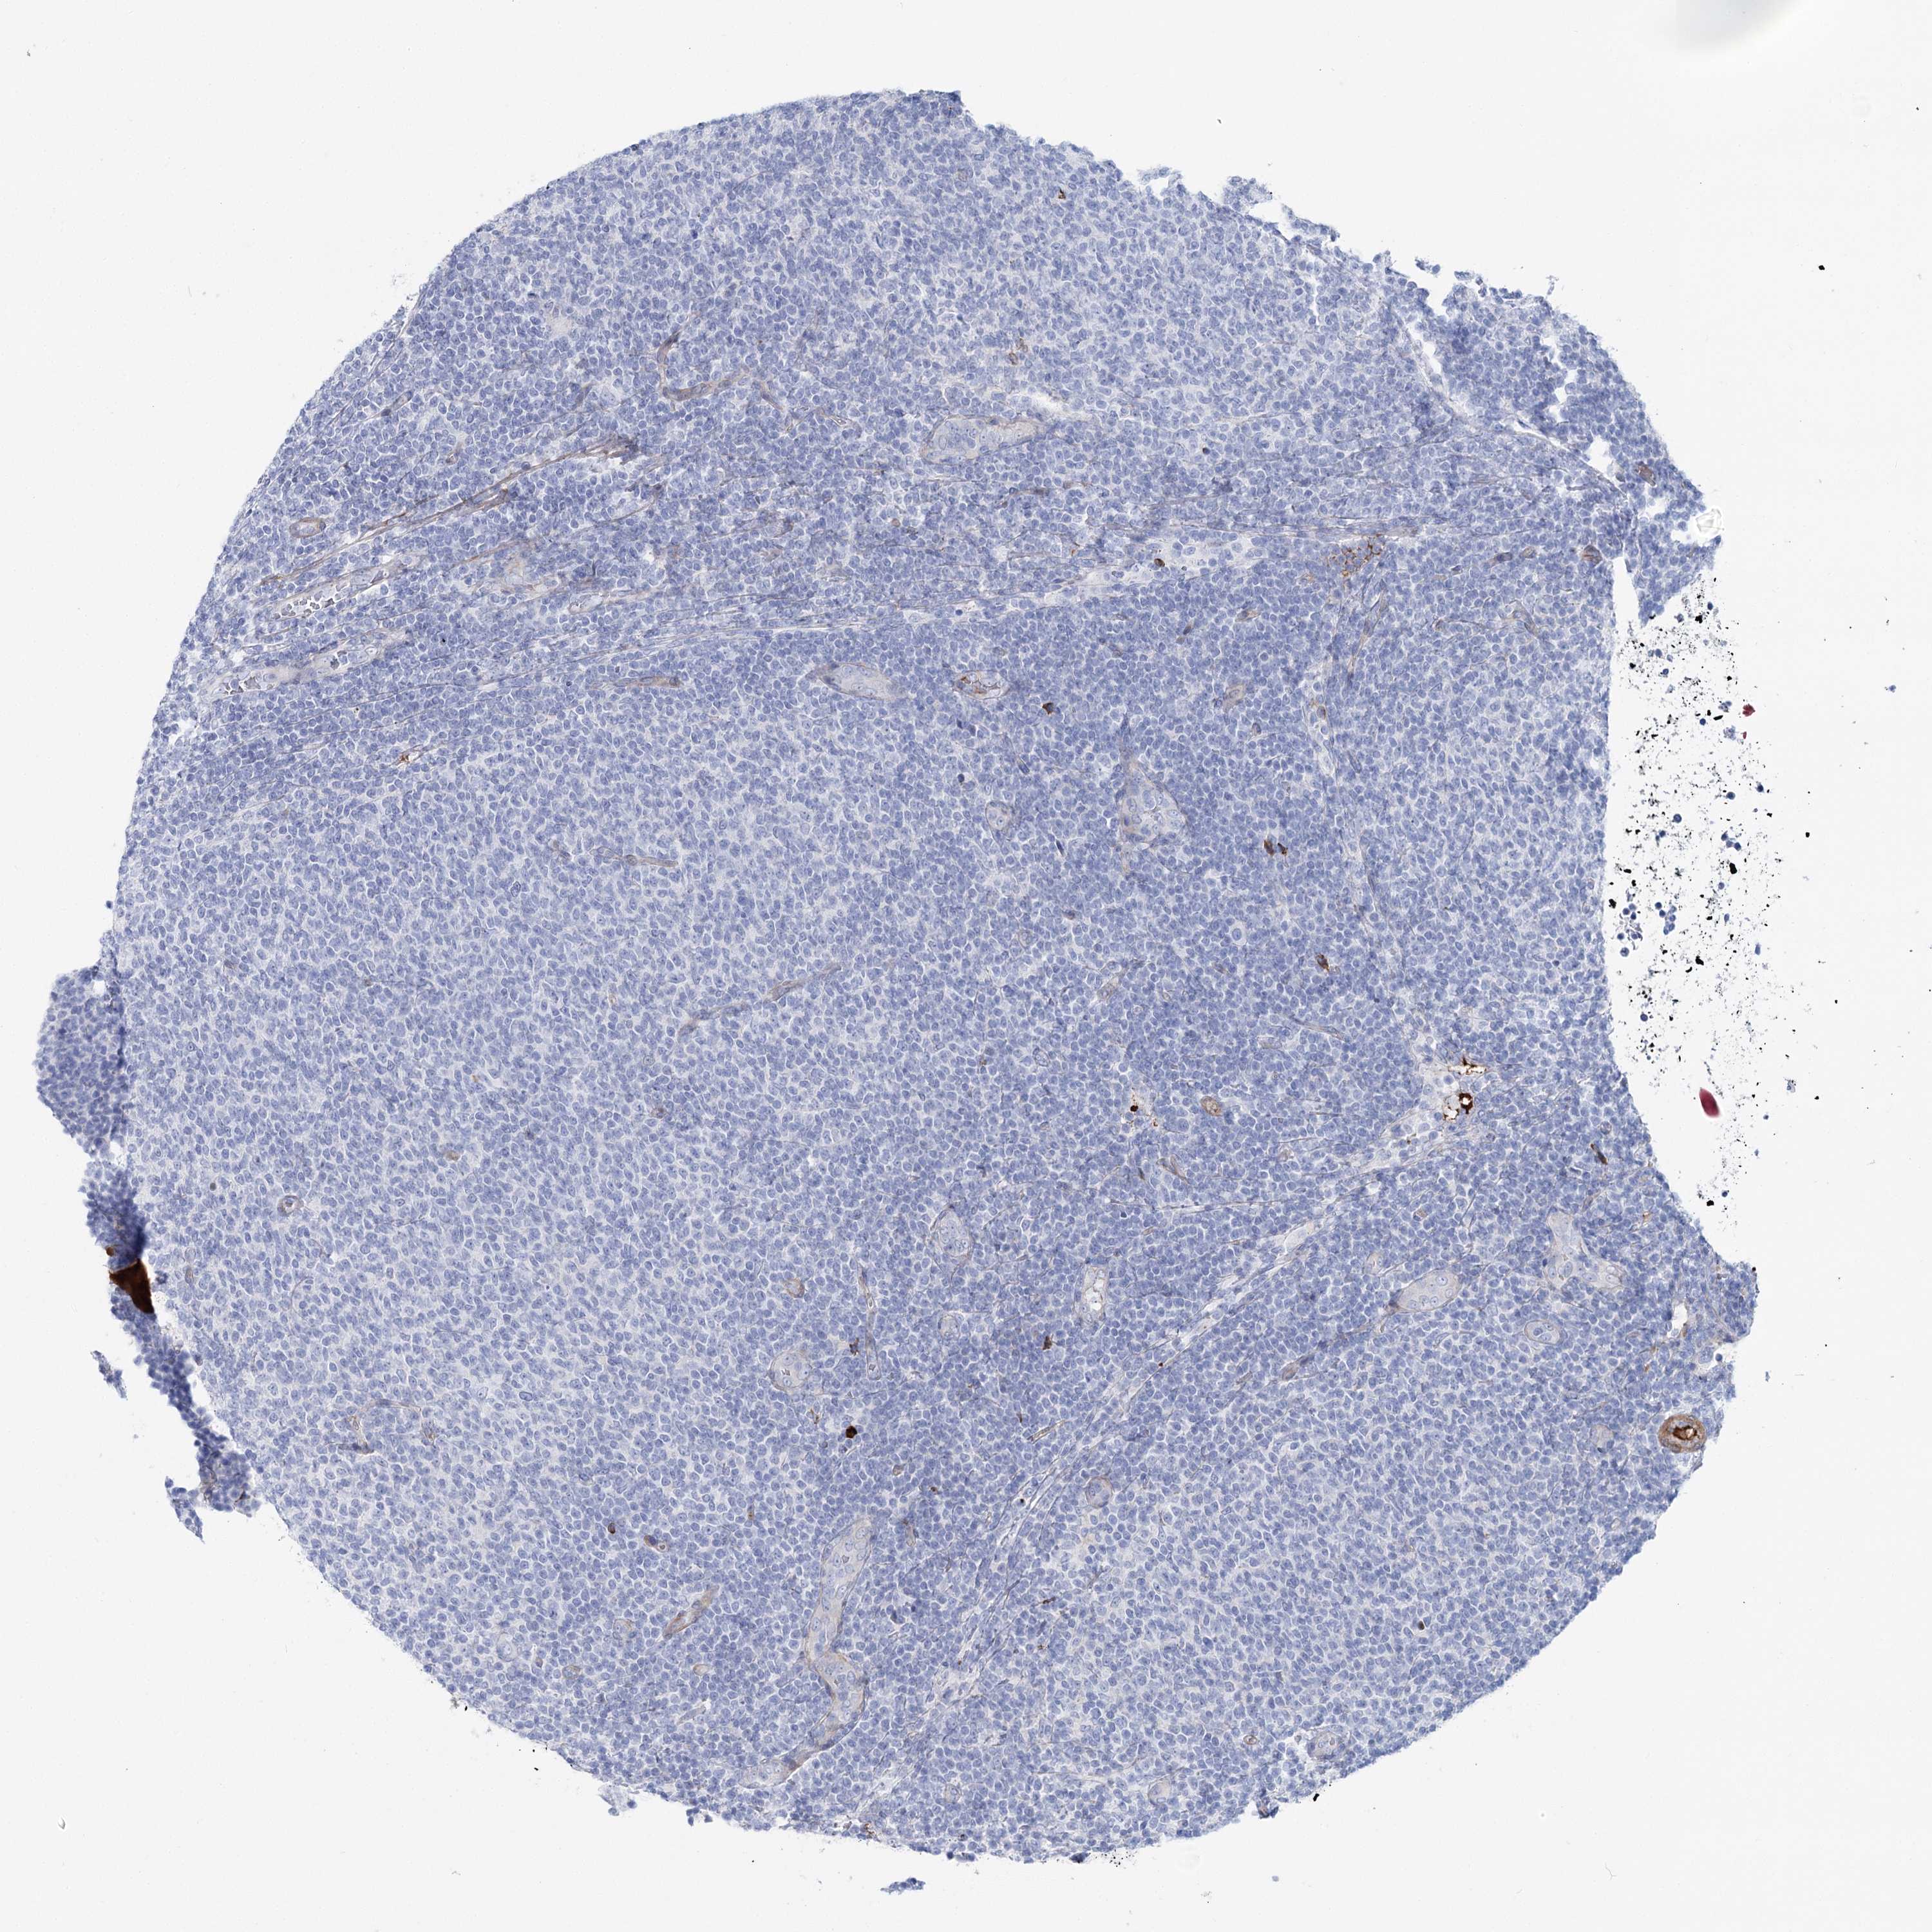

LYMPHOMA - Protein expressioni

A mouse-over function shows sample information and annotation data. Click on an image to view it in a full screen mode. Samples can be filtered based on level of antibody staining by selecting one or several of the following categories: high, medium, low and not detected. The assay and annotation is described here.

Each image is clickable and will lead to virtual microscopy that enables deeper exploration of all samples and also displays staining intensity scores, fraction scores and subcellular localization as well as patient and tissue information for each sample.

Antibody HPA036201

Hodgkin's disease, NOS

Malignant lymphoma, non-Hodgkin's type, High grade

Malignant lymphoma, non-Hodgkin's type, Low grade